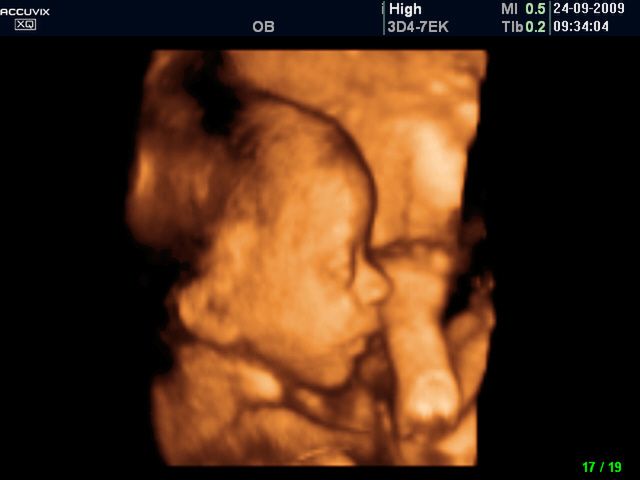

/ 5Płód w 26 tygodniu ciąży - ssanie palca

Dziecko często ssie swój palec